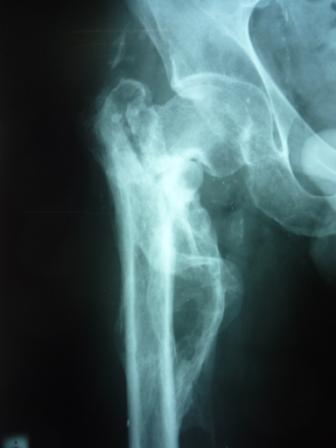

[Ortho] Сросшийся со смещением чрез-подвертельный перелом

Больной Н. 44 года травма 1,5 года назад июнь 2008 года чрез-под вертельный  перелом правого бедра. Во время лечения у больного развился алк делирий,  проводилось консертативное лечение перелома.

Беспокоят боли, укорочение конечности.

Укорочение 3 см. Ногу поднимает,  сгибание ограничено, ротационные движения в полном объеме.

На КТ перелом сросся за счет костной мозоли.